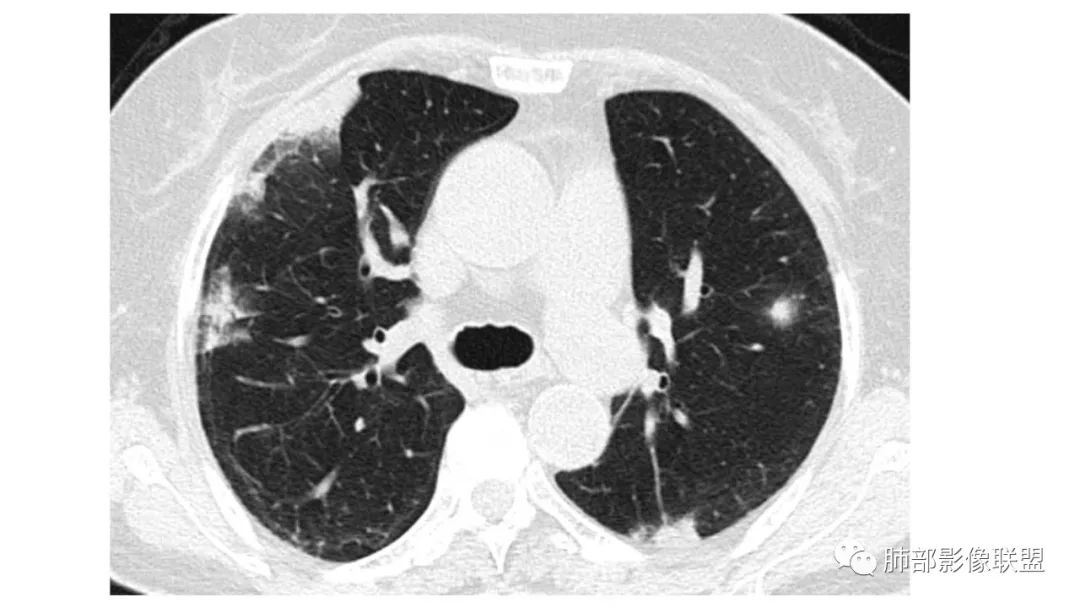

二、肺炎型

2、病灶常有一个主病灶,常位于下肺。后沿气道播散为多发病灶。

3、重力作用,叠瓦征。近叶间裂因重力效应,呈膨隆改变。

4、增强后不均匀强化,存在低强化区呈弱强化或无强化,因此可见“血管造影征。”血管毛糙与肺炎有统计学差异。

5、支气管粗细不均,呈“枯树枝征”,但与肺炎这一点鉴别不具有统计学差异。可发生支气管扩张

6、空腔形成,部分蜂窝状改变。

8、斑片常伴有结节,边缘清楚GGO或欠清楚。

9.粘液腺癌的变化规律:结节缓慢发展而来,向周围播散形成斑片后可快速进展,有时支气管镜后或粘液排出后局部可形成好转的假象。病灶可沿肺泡和支气管播散。

三、本例是一个误诊多年的病例,给我们很多启示:

2.粘液腺癌易伪装成肺炎的形态,尤其是当患者本身具有免疫色彩的时候,易误诊为间质性肺炎,或肺部感染。若治疗无效,取得病理很重要。

4.回到本例,左下肺病变两次好转,均未经过肿瘤治疗,第一次是支气管镜后,第二次是当其他病变都在进展的情况下,左下肺病变范围反而缩小趋于浅淡。